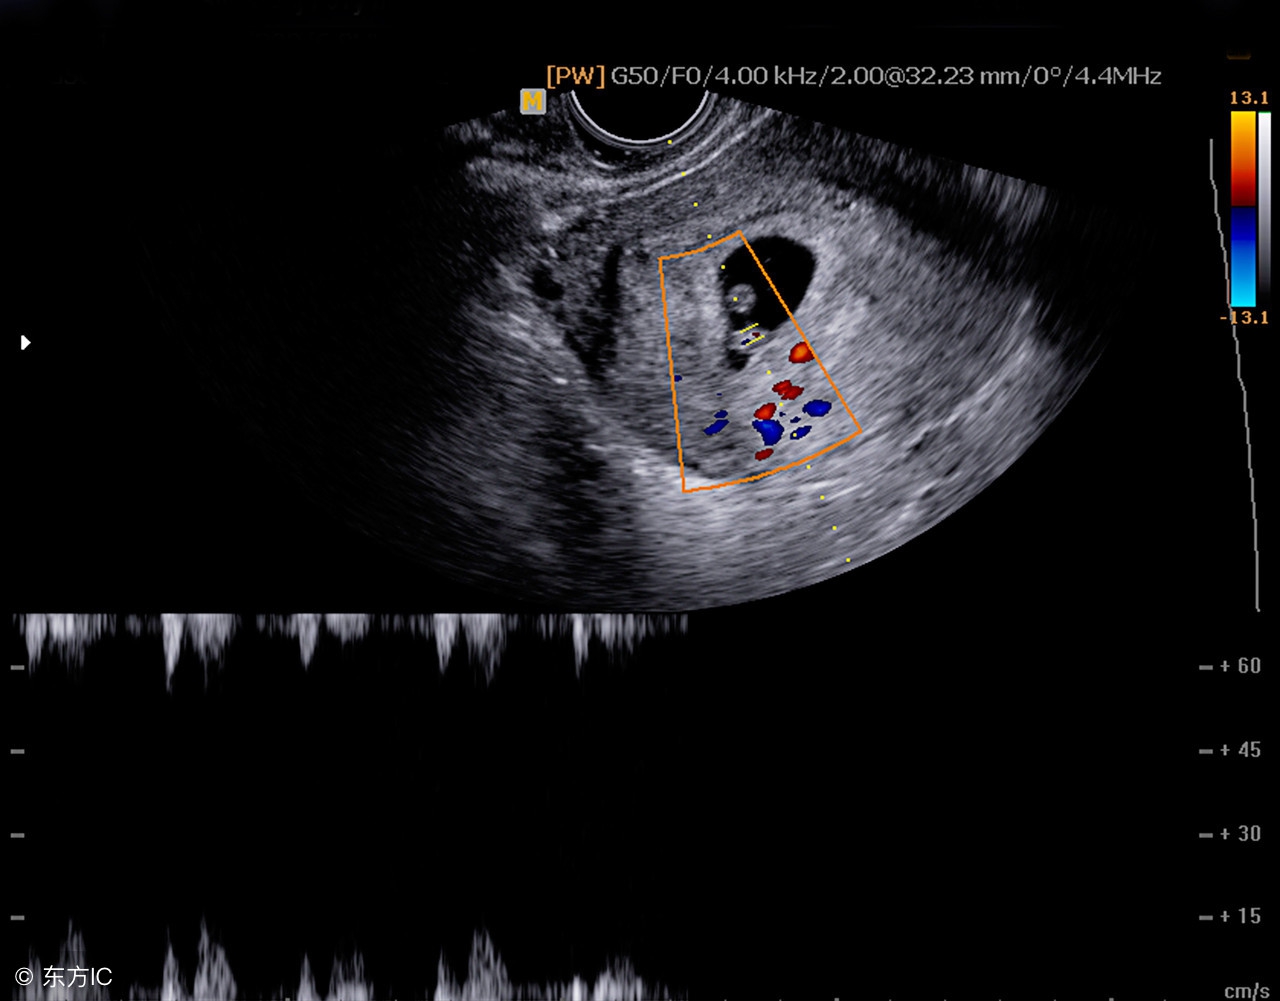

5周:胎儿长到0.4厘米,进入了胚胎期,羊膜腔扩大,原始心血管出现,可有搏动。B超可看见小胎囊,胎囊约占宫腔不到1/4,或可见胎芽。

6周:胎儿长到0.85厘米,胎儿头部、脑泡、额面器官、呼吸、消化、神经等器官分化,B超胎囊清晰可见,并见胎芽及胎心跳。

GS —— 胎囊,月经规则的妇女,停经35天,B超就可在宫腔内看到孕囊。在怀孕1.5个月时孕囊直径约2厘米,2.5个月时约5厘米。胎囊位置在子宫的宫底、前壁、后壁、上部、中部都属正常;形态圆形、椭圆形、清晰为正常;如胎囊为不规则形、模糊,且位置在下部,孕妇同时有腹痛或阴道流血时,可能要流产。用阴道超声波在四到五周、腹部超声波在六到七周就可以看出并可以描绘出来。到六周以后当子宫内GS看不出来时,可以怀疑是宫外孕。

3、胎心:有、强为正常,无、弱为异常。胎心频率正常为每分钟120-160次之间。